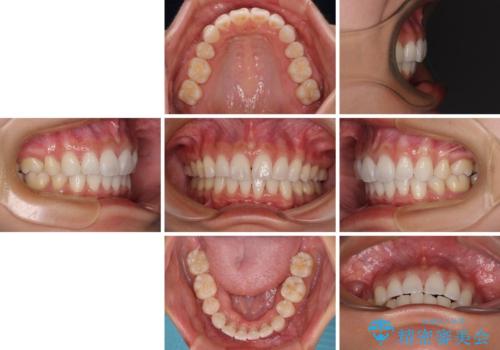

- 飛び出した前歯を気にして来院された患者様です。

口元を引っ込めるために上下左右の第一小臼歯4本を抜歯することとしました。

途中妊娠と出産がありましたが、予定よりも早く治療を終えることができました。